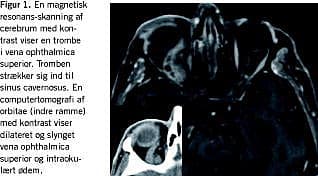

CT af orbitae hos vores patient viste en dilateret og slynget VOS med opladning i venevægen, men ikke i det tromboserede lumen. Der sås proptose, okulært ødem med normale ekstraokulære muskler og retrobulbært rum, og ingen infektionsfocus i bihulerne (Figur 1 ), dog kunne patologi i relation til SC såsom trombose eller karotikokavernøs fistel ikke udelukkes. Ved en MR-skanning blev der påvist en trombe, der var af ældre dato og strakte sig ind til SC dog uden patologi i forbindelse med denne (Figur 1). Desuden blev der fundet en patologisk opladning i pterygoidærmuskulaturen, hvilket kan være følger efter en peritonsillær eller retrofaryngeal infektion.